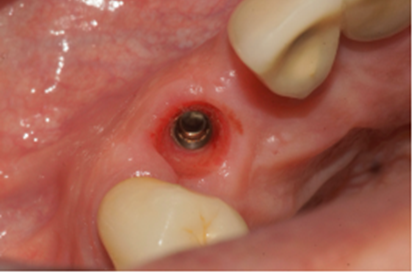

O caso clínico a seguir irá descrever o sucesso dessa nova realidade. Paciente J.C., de 65 anos de idade, do sexo masculino, compareceu em minha clínica com o elemento 13 fraturado (Figura 1). Após análise criteriosa da tomografia, foi planejada a exodontia e a instalação imediata do implante seguindo as novas tendências no posicionamento tridimensional, isto é, a melhor posição no rebordo na relação dento alveolar (Figura 2). Foi realizada a terapia medicamentosa com a administração de Amoxicilina 500 mg, de oito em oito horas durante sete dias, iniciando um dia antes do procedimento, e o uso de anti-inflamatório após a cirurgia, durante três dias. A exodontia foi realizada de forma atraumática, como sugerido na literarura (Figuras 3 e 4) e foi realizada a fresagem para a instalação de um implante Due Cone Implacil De Bortoli (conexão morse) de 3.5 x 13 mm, que foi estabilizado a 46 Ncm (Figuras 5, 6 e 7). Após a instalação, o gap foi preenchido com biomaterial, um cicatrizador de 5.5 X 3.5 mm (diâmetro/altura) foi instalado e o tecido foi suturado ao seu redor, protegendo assim o biomaterial (Figura 8).

Figura 8 – Cicatrizador de 5.5 X 3.5 mm instalado